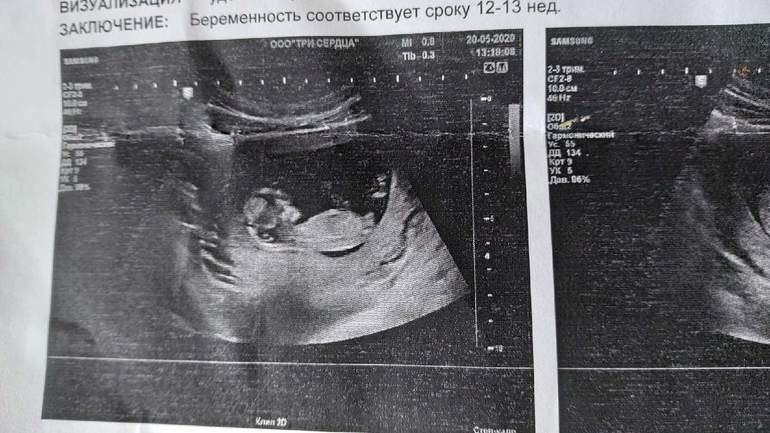

Пол малышаНашла узи, кого видите? На кого похоже?😁

Узист мальчика увидел, я все кручу верчу снимки мне вообще ничего не видно😁Говорят они как то по углу предполагают

Ну по первому фото мне кажется 100% девочка. У меня у дочки даже больше вверх бугорок торчал в 15 недель

На самом первом фото бугорок под углом,похож на мальчишеский...А дальше просто может так сделано фото)Но на таком сроке,если узист не опытный,то могут быть ошибки,конечно.У мальчиков обычно просто более выраженный угол вверх...

Больше похоже на девочку. Хотя небольшой угол отклонения как будто есть, но совсем мало

У мальчиков обычно сильнее задран бугорок. На этом фото похоже на девочку. Недели через 2 будет уже хорошо видно, если пацан

На девочку очень похоже, где ваш Узист мальчика увидел🤔найду фото покажу как мальчики выглядят.